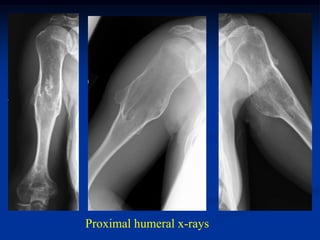

Case #625.1                 Multiple hereditary exostoses

Proximal humeral x-rays